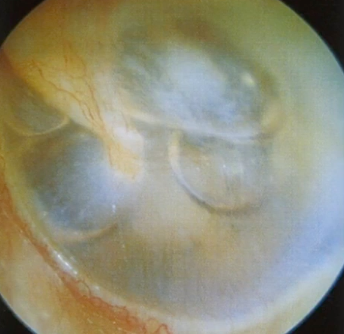

9

Q

A

Otitis media aguda

( timpano abombado hiperémico: FASE PRECOZ )

How well did you know this?